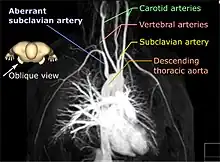

Magnetic resonance angiography (MRA) is a group of techniques based on magnetic resonance imaging (MRI) to image blood vessels. Magnetic resonance angiography is used to generate images of arteries (and less commonly veins) in order to evaluate them for stenosis (abnormal narrowing), occlusions, aneurysms (vessel wall dilatations, at risk of rupture) or other abnormalities. MRA is often used to evaluate the arteries of the neck and brain, the thoracic and abdominal aorta, the renal arteries, and the legs (the latter exam is often referred to as a "run-off").

Time-of-flight (TOF) or inflow angiography, uses a short echo time and flow compensation to make flowing blood much brighter than stationary tissue. As flowing blood enters the area being imaged it has seen a limited number of excitation pulses so it is not saturated, this gives it a much higher signal than the saturated stationary tissue. As this method is dependent on flowing blood, areas with slow flow (such as large aneurysms) or flow that is in plane of the image may not be well visualized. This is most commonly used in the head and neck and gives detailed high-resolution images. It is also the most common technique used for routine angiographic evaluation of the intracranial circulation in patients with ischemic stroke.[1]

MRA has been successful in studying many arteries in the body, including cerebral and other vessels in the head and neck, the aorta and its major branches in the thorax and abdomen, the renal arteries, and the arteries in the lower limbs. For the coronary arteries, however, MRA has been less successful than CT angiography or invasive catheter angiography. Most often, the underlying disease is atherosclerosis, but medical conditions like aneurysms or abnormal vascular anatomy can also be diagnosed.